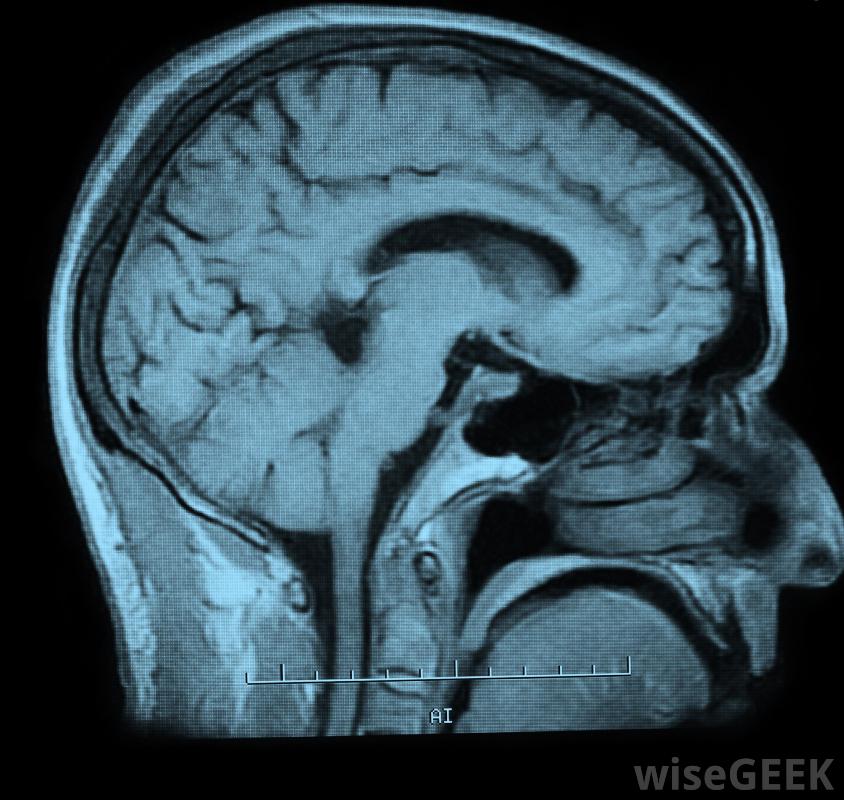

腰椎穿刺是一種醫學方法,通常被稱為脊椎穿刺。這個過程包括用針從背部取出腦脊液(CSF)。腦脊液通過在內部結構周圍起緩沖作用來保護大腦和脊髓。通常情況下,將針插入腰椎,或者背部下部。這種手術通常在醫院里進行,不過,也可以在門診部進行。腰椎穿刺術后可能會出現頭痛和頸部放射狀疼痛醫生可以用腰椎穿刺來診斷疾病。這種方法通常用于診斷中樞神經系統疾病。它也可以用來確認可疑的腦出血。比如腦膜炎,神經系統的炎癥和脊髓和腦癌同樣可以通過這個手術得到證實。患有神經系統疾病的人可能更頻繁地進行腰椎穿刺可以在腰椎穿刺之前進行腦部掃描。有時,會通過腰椎穿刺來給藥。例如,脊髓麻醉劑有時是這樣給藥的例,脊柱診斷試驗所需的染料可通過本程序注射通常,腰椎穿刺是作為一種治療方法來減輕大腦或頭骨的壓力。一旦腦脊液被取出,腰椎穿刺通常會直接送到實驗室接受仔細檢查。腰椎穿刺會清除一些保護脊髓的腦脊液一般情況下,這種類型的醫療程序不需要很好的準備。服用常規藥物的人可能會被建議在進行腰椎穿刺之前停止某些處方的治療。一些醫生可能會在這個過程之前進行計算機斷層掃描或磁共振檢查核磁共振成像(MRI)。這些檢查可以對大腦或脊柱進行全面檢查。一般來說,醫生會在手術前讓患者知道他或她是否需要做任何特別的事情。病人需要住院治療在背部穿刺時,通常會在背部注射消毒劑,用于麻醉,將針頭插入腰椎,收集腦脊液。有些病人可能會被要求以某種方式定位,以便于液體的提取。醫生通常建議病人躺下服用手術后容易。特別是劇烈的活動需要避免一整天腰椎穿刺術后最大的主訴通常是背部疼痛或頭痛。對于這兩種情況,建議服用止痛藥。雖然如果疼痛加劇并出現其他并發癥,則應聯系醫生可能需要腰椎穿刺,用壓力計測量腦脊液壓力。